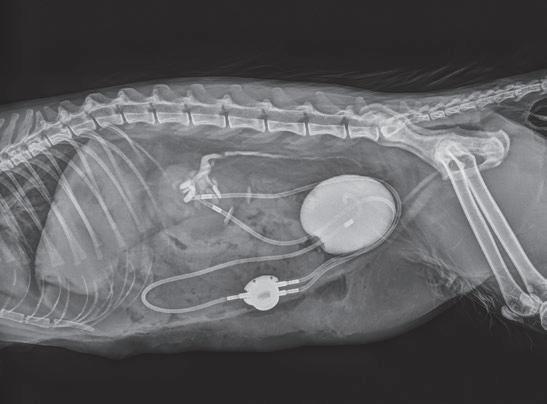

La radiología intervencionista es una especialidad que se encarga del diagnóstico y tratamiento de una gran cantidad de patologías de una forma mínimamente invasiva. Para realizar estos procedimientos es imprescindible disponer del equipamiento adecuado, tener nociones tanto de la instrumentalización como de las diferentes técnicas, y conocer con precisión la anatomía del paciente. Se trata de técnicas cada vez más implementadas en la clínica diaria ya que permiten solucionar diferentes patologías con una menor agresión a nivel tisular, una rápida recuperación, son procedimientos sin dolor, rápidos y seguros, suponen un menor coste respecto a otras cirugías invasivas, y constituyen una alternativa terapéutica a pacientes que no se pueden operar de forma convencional. Entre las más frecuentes destaca el cierre del conducto arterioso persistente, valvuloplastias en estenosis pulmonar, oclusión de shunts portosistémicos, implantación de marcapasos y colocación de stents

En 1953, el Dr. Sven Seldinger describió la colocación percutánea de catéteres vasculares mediante acceso con aguja, técnica que posteriormente se denominó método Seldinger, y que sentó las bases del desarrollo de la radiología intervencionista. En 2005, el Dr. Chick Weisse creó el primer servicio veterinario de radiología intervencionista en la Facultad de Veterinaria de la Universidad de Pensilvania. Desde entonces, esta especialidad ha logrado grandes avances permitiendo el desarrollo de nuevas técnicas y dispositivos, así como un número cada vez mayor de indicaciones para estas técnicas quirúrgicas.

La radiología intervencionista se realiza mediante un abordaje guiado por distintas técnicas de imagen como, por ejemplo, la ecografía, la fluoroscopia o la tomografía computarizada, para alcanzar la zona a diagnosticar o tratar.

La radiología intervencionista, también conocida como radiología vascular e intervencionista, es una especialidad que se encarga del diagnóstico y tratamiento de una gran cantidad de enfermedades de una manera mínimamente invasiva. Se realiza mediante un abordaje guiado por distintas técnicas de imagen como, por ejemplo, la ecografía, la fluoroscopia o la tomografía computarizada, para alcanzar la zona a diagnosticar o tratar.

La radiología vascular e intervencionista ofrece una alternativa segura y eficaz a la cirugía en muchas enfermedades. Entre sus ventajas para el paciente destaca una menor agresión a nivel tisular, una rápida recuperación, procedimientos sin dolor, rápidos y seguros, un menor coste respecto a otras muchas cirugías con mis-

imágenes basadas en rayos X y posteriormente las convierte en una señal de vídeo en tiempo real. Estas imágenes pueden manipularse ofreciendo funciones como la angiografía de sustracción digital, mapeo vascular y ampliación. Respecto a una radiografía, la exposición de rayos X necesaria para realizar una fluoroscopia es baja, pero debido a la duración de las series de imágenes que habitualmente se toman, el nivel de exposición en los pacientes suele ser elevado. Por lo tanto, es importante controlar el tiempo de exposición y llevar un registro de este. El fluoroscopio debe estar situado en una sala adecuada para su uso seguro, y todo el personal que entre en la sala de fluoroscopia debe protegerse de la radiación utilizando un delantal plomado, protectores de tiroides y gafas plomadas.